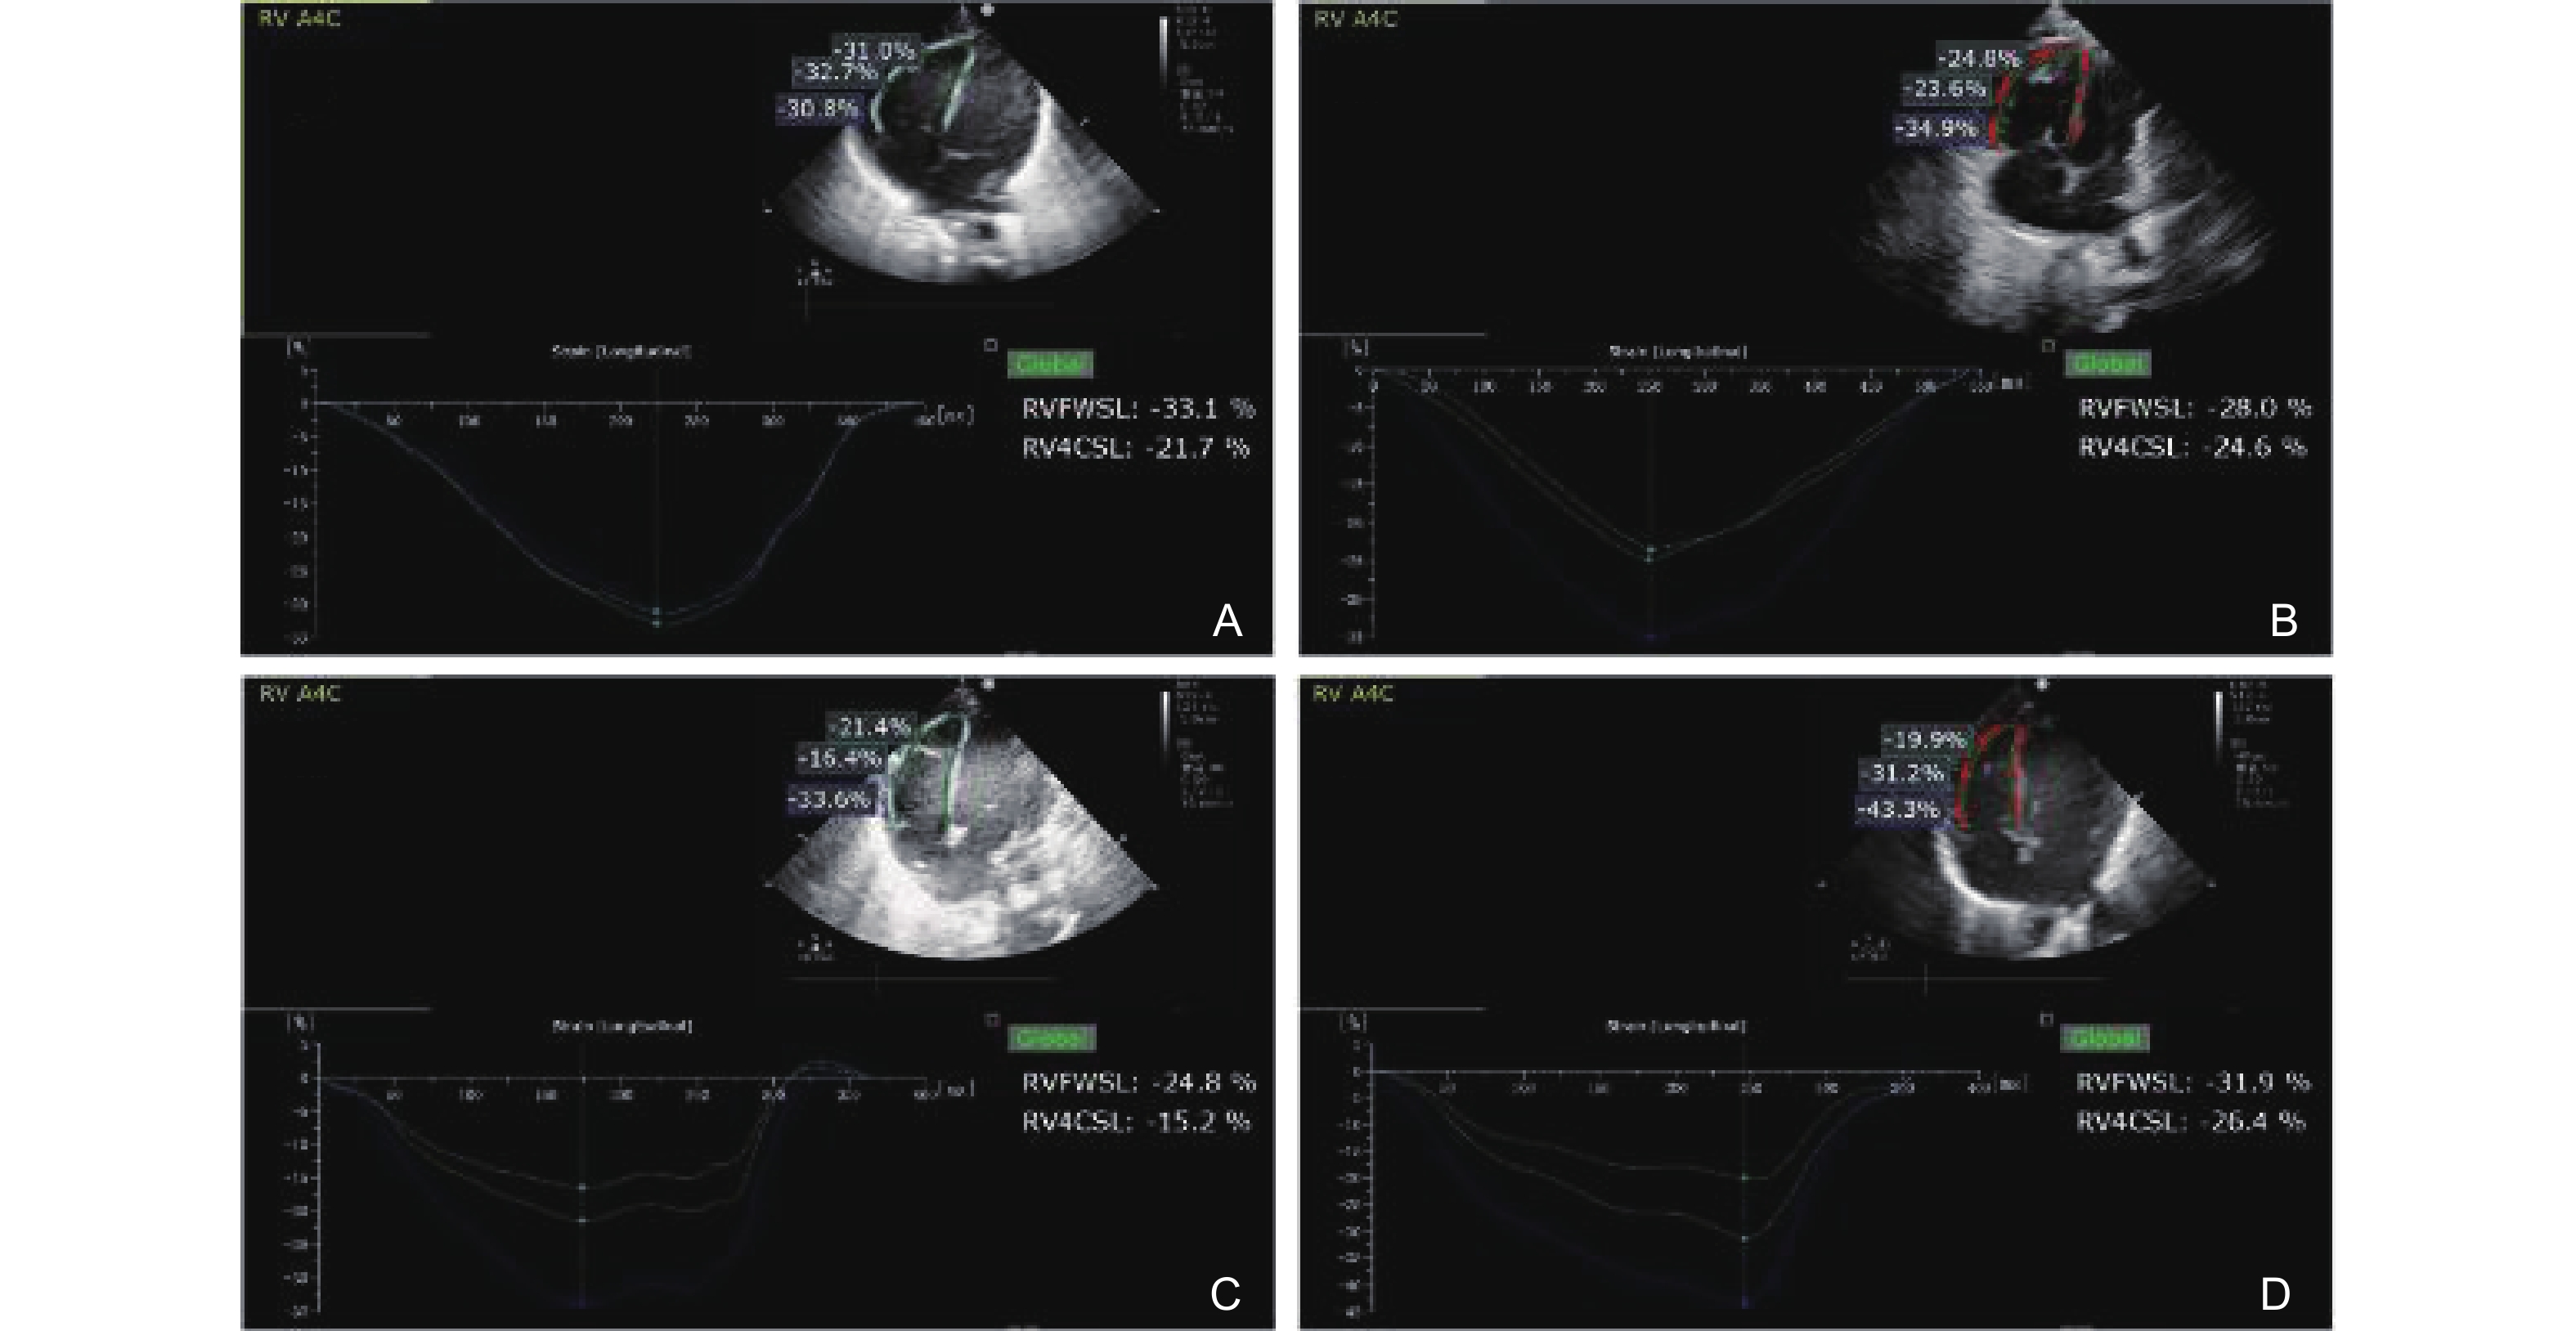

Yang H, Feng Q, Su Z, Chen S, Wu F, He Y. The increased longitudinal basal-to-apical strain ratio in the right ventricular free wall is associated with neonatal pulmonary hypertension. Eur J Pediatr 2024; 183: 5395-5404.

|

Pirat B, McCulloch ML, Zoghbi WA. Evaluation of global and regional right ventricular systolic function in patients with pulmonary hypertension using a novel speckle tracking method. Am J Cardiol 2006; 98: 699-704.

Fukuda Y, Tanaka H, Sugiyama D, Ryo K, Onishi T, Fukuya H, et al. Utility of right ventricular free wall speckle-tracking strain for evaluation of right ventricular performance in patients with pulmonary hypertension. J Am Soc Echocardiogr 2011; 24: 1101-1108.

Tunthong R, Salama AA, Lane CM, Fine NM, Anand V, Padang R, et al. Right ventricular systolic strain in patients with pulmonary hypertension: clinical feasibility, reproducibility, and correlation with ejection fraction. J Echocardiogr 2023; 21: 105-112.

Liu Q, Hu Y, Chen W, Yao T, Li W, Xiao Z, et al. Evaluation of right ventricular longitudinal strain in pediatric patients with pulmonary hypertension by two-dimensional speckle-tracking echocardiography. Front Pediatr 2023; 11: 1189373.

Li Y, Xie M, Wang X, Lu Q, Fu M. Right ventricular regional and global systolic function is diminished in patients with pulmonary arterial hypertension: a 2-dimensional ultrasound speckle tracking echocardiography study. Int J Cardiovasc Imaging 2013; 29: 545-551.